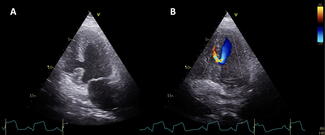

Aref El Nasasra, MD; Artyom Star, MD; Sergio L. Kobal, MD; Carlos Cafri, MD; Hilmi Alnsasra, MD

A 63-year-old man underwent mitral valve repair with a 28-mm Cosgrove-Edwards annuloplasty ring (Edwards Lifesciences) in 1999 due to severe primary mitral regurgitation. He did well until recently, when he was recurrently admitted with...